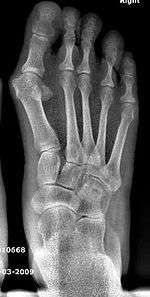

Syndesmosis procedure addresses specifically the two fundamental problems of metatarsus primus varus deformity that gives rise to the bunion deformity. They are leaning and instability of the first metatarsal bone . Syndesmosis procedure uprights the leaning first metatarsal bone with strong binding sutures between it and the second metatarsal bone (Fig. 2) and then also stabilizes it uniquely by creating a fibrous connecting bridge between these two bones (Fig. 3,4). First metatarsal bone can be readily realigned is because by definition of the metatarsus primus varus deformity its first metatarsal is abnormally loose and mobile.